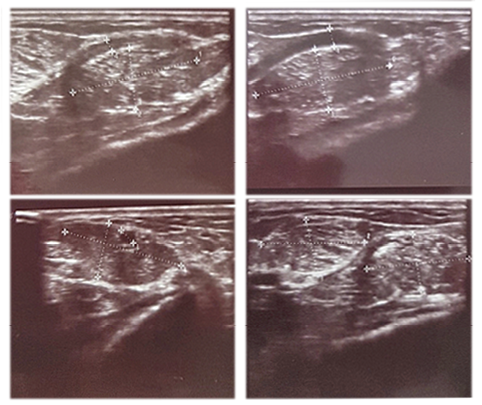

Sonoscopy revealed a non-encapsulated mass, measuring 6 cm at its largest diameter (Figure 3).

Cheiralgia%20figure3.png

Figure 3. Ultrasound image of the lesion

The exact position of the lesion coincides with the anatomical location where SBR, piercing the deep fascia, approaches the subcutaneous layer. The mass was extirpated and confirmed to be a lipoma (Figures 4, 5).